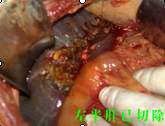

“病情嚴(yán)重,盡快手術(shù)?!薄T主任如是說。患者入院后,譚主任立即召集醫(yī)務(wù)人員進(jìn)行術(shù)前討論,安排醫(yī)生完善各種術(shù)前檢查,制定周密的手術(shù)方案。第二天,他即帶領(lǐng)腫瘤外科經(jīng)驗(yàn)豐富的醫(yī)生為患者實(shí)施了肝門部膽管癌切除+膽囊切除+左半肝切除,右肝管空腸R-Y吻合術(shù)。在手術(shù)中,由于患者膽囊梗阻部位非常高,腫塊生長長度已達(dá)到左右肝總管交界處,手術(shù)過程中極容易損傷門靜脈、肝動(dòng)脈及腔靜脈。先切除膽囊,后分離肝、十二指腸韌帶,骨骼化門靜脈、膽總管、肝動(dòng)脈。見腫塊位于高位膽總管,予以切除左肝總管及肝左葉,行R-Y吻合,整個(gè)手術(shù)僅用了6個(gè)小時(shí),術(shù)中出血極少,手術(shù)過程非常順利,術(shù)后及時(shí)給予抑酸、抗炎、護(hù)肝補(bǔ)液等對癥支持治療。經(jīng)過精心地治療和周到地護(hù)理,現(xiàn)患者恢復(fù)良好。據(jù)統(tǒng)計(jì),此手術(shù)切除機(jī)率不到5%。